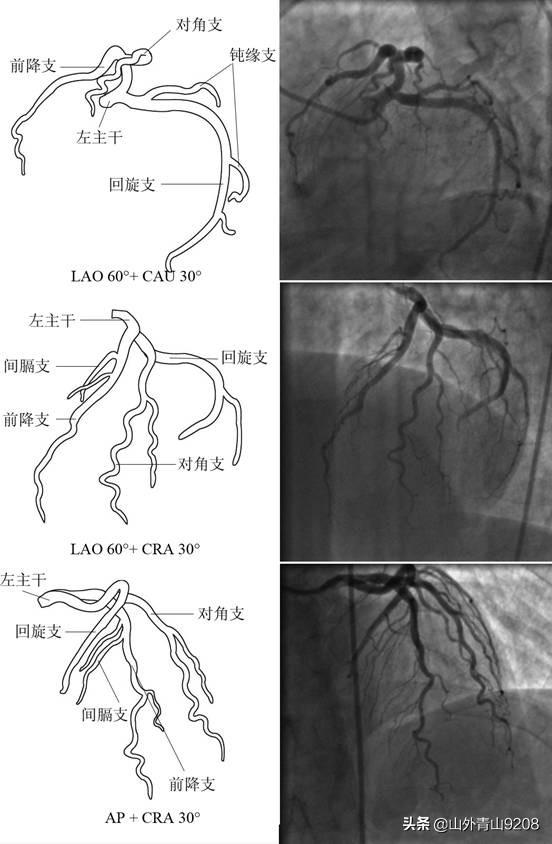

医学影像—心脏大血管摄影检查技术ppt

心脏大血管的影像学解剖ppt